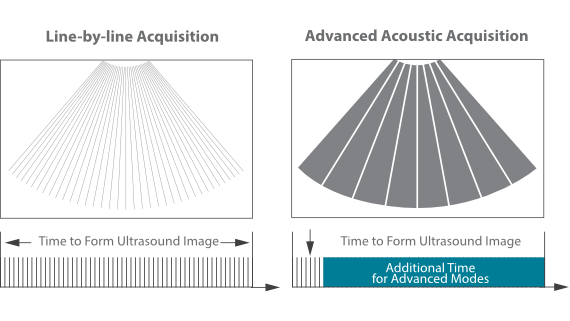

MX7? ??? ZST+ ???? ???? ??? ??? ???? ?? ??? ?? ??? ??? ??? ?? ???? ?? ???? ?????? ?????. ??? ?? ??? ?? 8??? ??? ??? ?? ?? ??? ?? ???? ??? ?????. ?? ?? ? ?? ??? ?? ??? ??? ? ????.